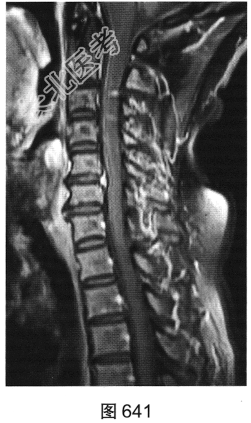

- 多项选择题3.[提示]患者保守治疗2个月后复查MRI,见图638~图642。复查的MRI图像与前次比较, 有哪些影像学变化( )

A、病变明显变小

B、颈前软组织强化

C、增强后未见强化

D、增强后可见小片状强化

E、C

间盘信号有变化F、硬膜囊及颈髓受压缓解

关注下方微信公众号,搜题查看答案

- 多项选择题4.根据复查的MRI表现,该患者可能的诊断是( )

A、椎间盘脱出、髓核游离

B、硬膜外血肿

C、神经纤维瘤

D、后纵韧带骨化

E、神经鞘瘤

F、脊柱淋巴瘤